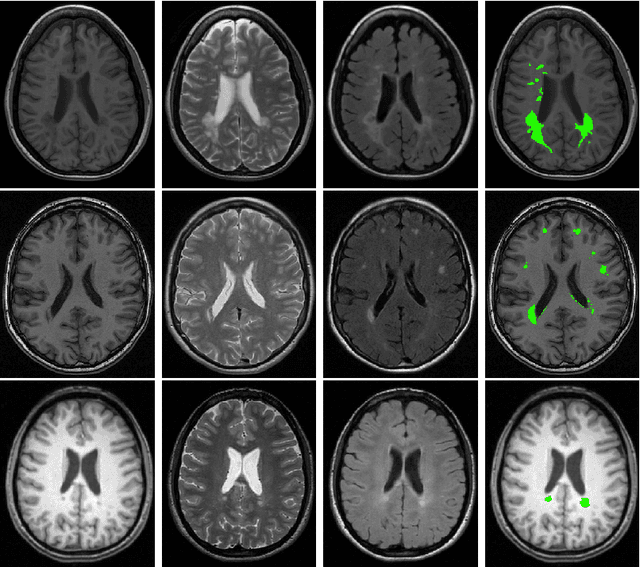

Abstract:Supervised learning has been very successful for automatic segmentation of images from a single scanner. However, several papers report deteriorated performances when using classifiers trained on images from one scanner to segment images from other scanners. We propose a transfer learning classifier that adapts to differences between training and test images. This method uses a weighted ensemble of classifiers trained on individual images. The weight of each classifier is determined by the similarity between its training image and the test image. We examine three unsupervised similarity measures, which can be used in scenarios where no labeled data from a newly introduced scanner or scanning protocol is available. The measures are based on a divergence, a bag distance, and on estimating the labels with a clustering procedure. These measures are asymmetric. We study whether the asymmetry can improve classification. Out of the three similarity measures, the bag similarity measure is the most robust across different studies and achieves excellent results on four brain tissue segmentation datasets and three white matter lesion segmentation datasets, acquired at different centers and with different scanners and scanning protocols. We show that the asymmetry can indeed be informative, and that computing the similarity from the test image to the training images is more appropriate than the opposite direction.